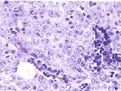

癌細胞多為類圓形或棱形,胞漿少,類似淋巴細胞、燕麥細胞型和中間型可能起源於神經外胚層的Kulchitiky細胞或嗜銀細胞。核細胞漿內含有神經分泌型顆粒,具有內分泌和化學受體功能,能分泌5-羥色胺、兒茶酚胺、組胺、激肽等肽類物質,可引起副癌綜合徵(paraneoplastic syndrome)。